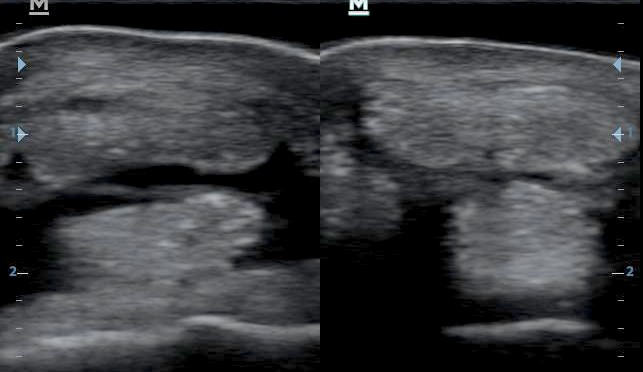

A mérések azt mutatják, hogy a sérült bal oldal jelentősen megvastagodott az ép oldalhoz viszonyítva. Fontos az aszimmetrikus alak felismerése is!